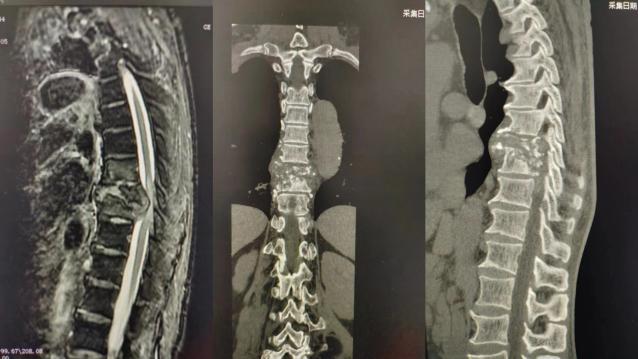

近日,我院脊柱外科收治了一名胸椎结核合并截瘫的患者,该患者属于结核活动期,胸背部疼痛难忍,伴随结核中毒症状明显,无自主排尿排便;脐水平以下深浅感觉障碍,双下肢肌力0级,影像学提示胸7、8、9椎体破坏严重;结核病灶脓液、肉芽组织、坏死物质及死骨等压迫脊髓,脊柱稳定性受到破坏,产生后凸畸形;同时患者既往有腹主动脉夹层病史,增添了更多意外风险。患者及家属多处求医未果,将希望寄托于我院脊柱外科。